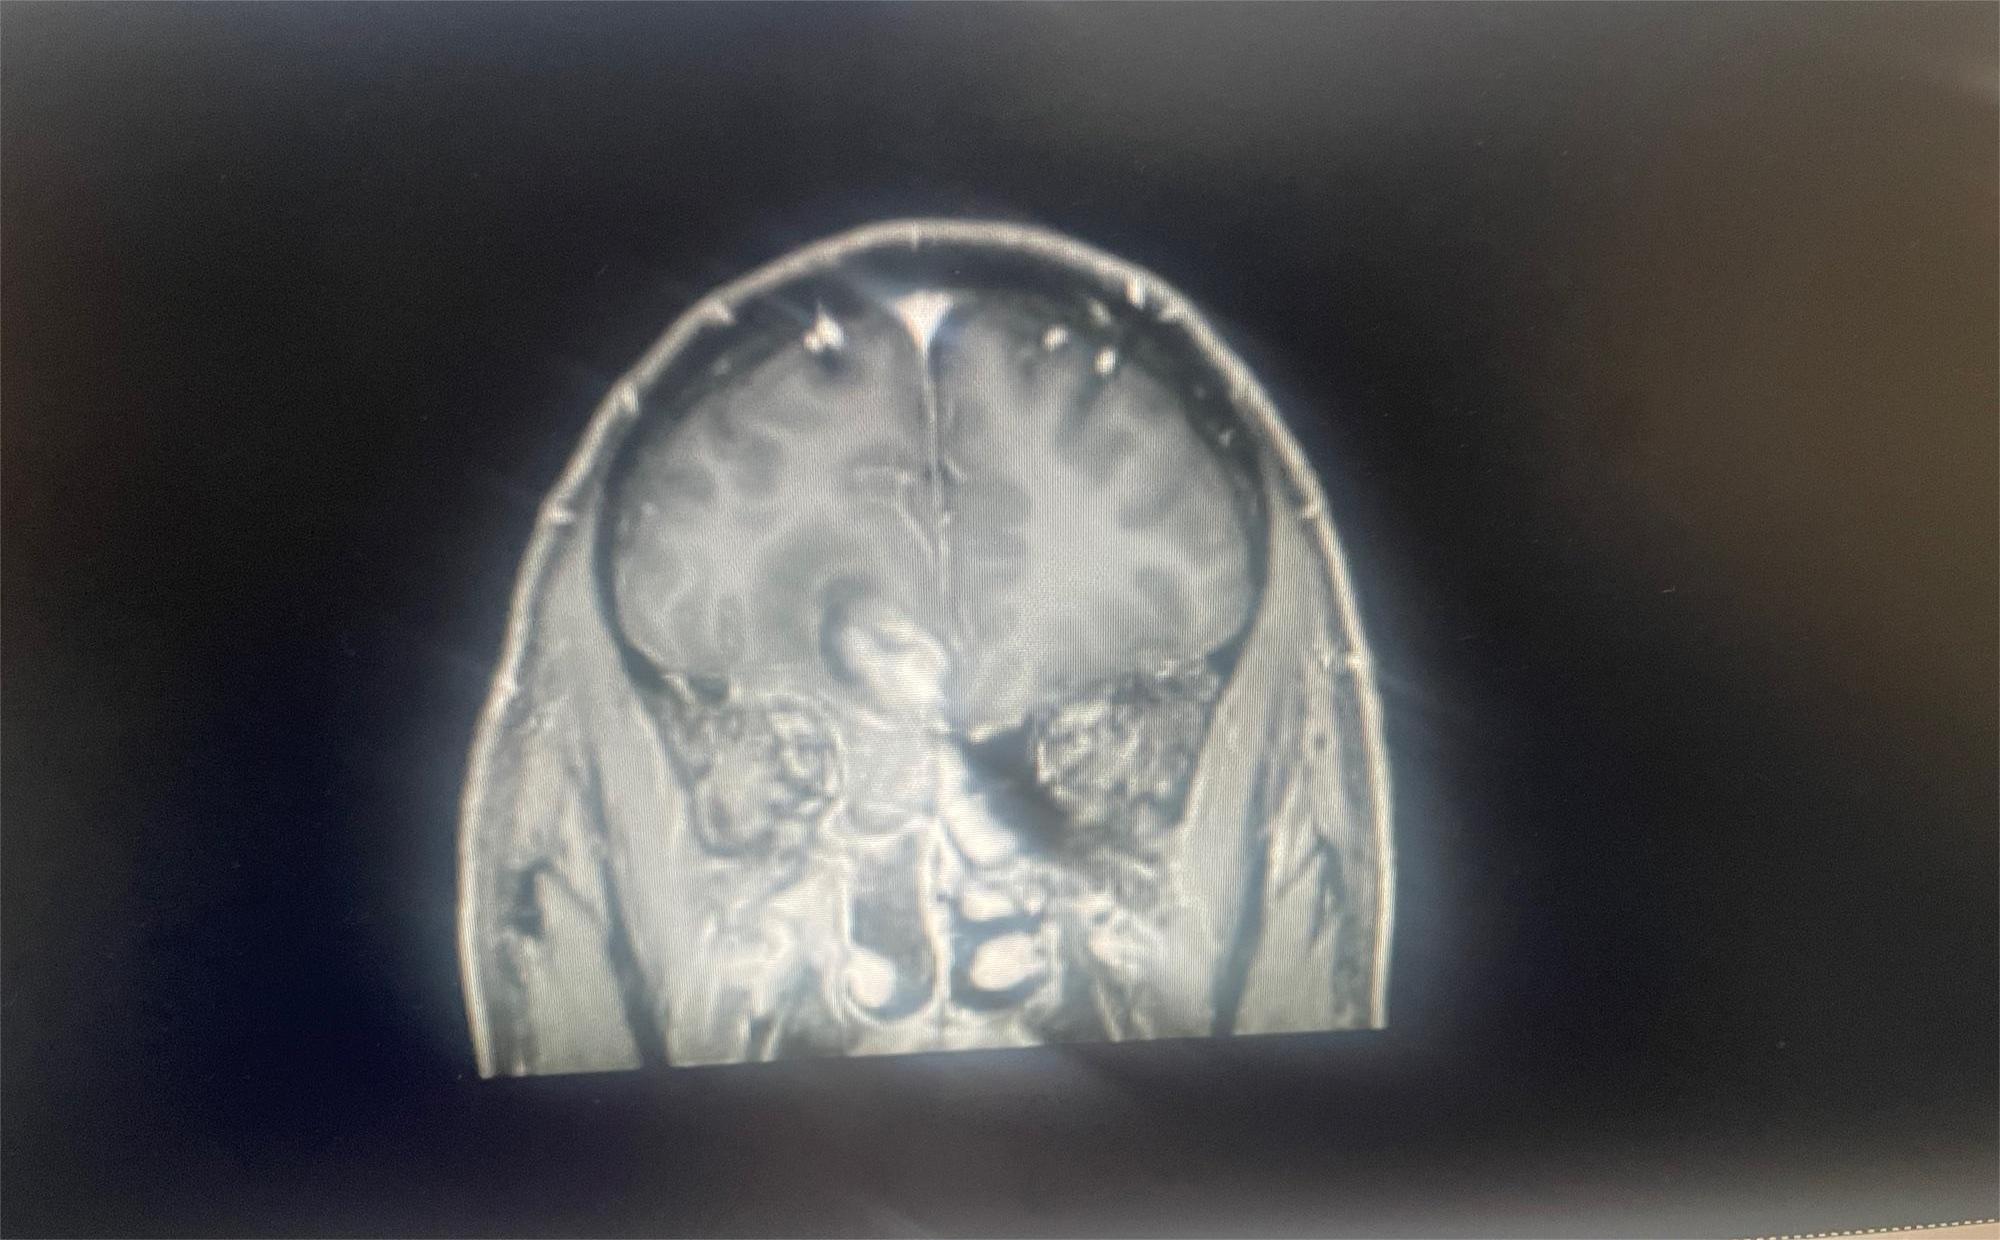

这是我83岁奶奶的报告,哪位朋友能帮忙看看这是到什么阶段了,发展到晚期还有多长时间。 医生说肿瘤挨着血管,做不了手术,年...

共1张

这是早期还是晚期的肿瘤呢